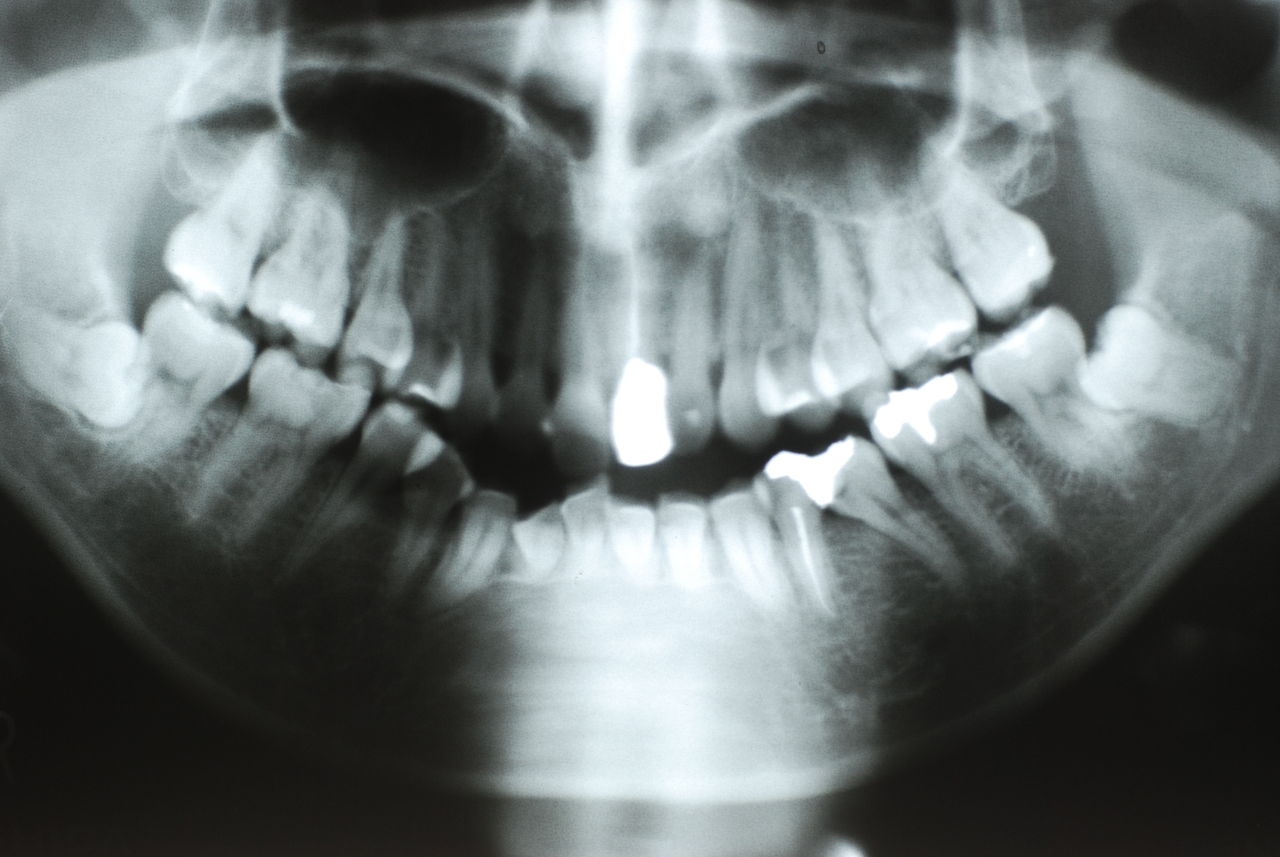

下記はかなりうまくいった方です。

平成9年治療、虫歯と神経の処置、歯周病の治療

![a7fa4f9f-s[1]](https://livedoor.blogimg.jp/netdental/imgs/4/2/42470ffa.jpg)

2012,7月来院

欠けたところを埋めておしまいです。